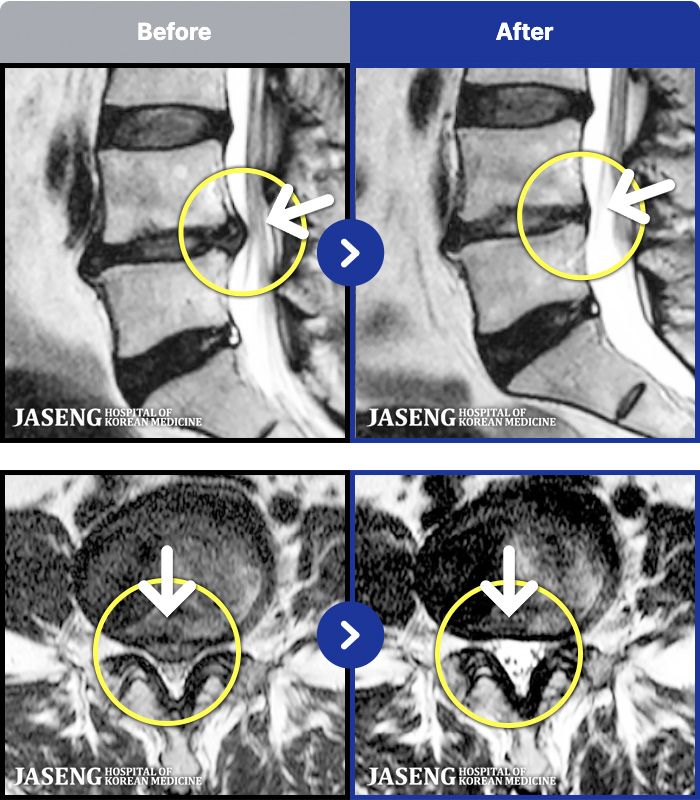

- MRI ġ

MRI ġ

1,296 MRI ũ ʸ Ȯϼ.